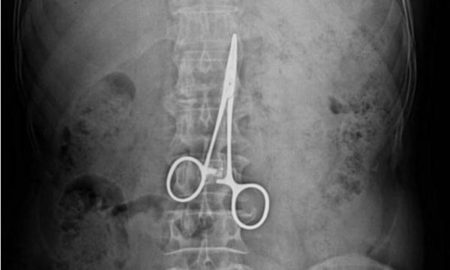

Univerzitetska klinička bolnica (SKB) Mostar moraće da isplati A.P. (41), 10.000 evra plus kamate i troškove sudskog postupka, zbog lekarske greške tokom...